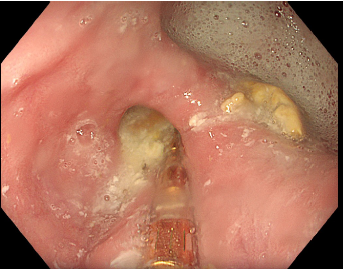

La EDA mostró un esófago tortuoso con presencia de tres divertículos en el tercio distal, localizados a 34, 37 y 39 cm de la arcada dentaria, siendo el de mayor tamaño de aproximadamente 2 cm y con discreto contenido líquido en su interior. Además, se describió una hernia de hiato pequeña, sin lesiones asociadas y angiodisplasias duodenales como hallazgo incidental.

Dada la conocida asociación entre los divertículos epifrénicos y los trastornos motores esofágicos, se decidió completar el estudio mediante manometría esofágica. Debido a la mayor dificultad técnica y al riesgo potencial de complicaciones en presencia de divertículos esofágicos, la colocación del catéter se realizó bajo control endoscópico con el objetivo de minimizar riesgos y asegurar su correcta posición (Imagen 1).

Desde el punto de vista técnico, la presencia de divertículos esofágicos, especialmente cuando alcanzan tamaños considerables, puede dificultar la progresión del catéter de manometría y aumentar el riesgo de posicionamiento inadecuado o de complicaciones. En este contexto, la colocación del catéter bajo control endoscópico constituye una estrategia útil que permite asegurar su correcta progresión a través de la luz esofágica y reducir el riesgo de iatrogenia, facilitando así la realización segura del estudio manométrico.

Foto 1. Divertículo esofágico epifrénico visualizado mediante gastroscopia durante la colocación de la sonda de manometría. Se evidencia retención alimentaria y progresión de la sonda por la luz esofágica hacia el estómago, observándose a la derecha un divertículo epifrénico de gran tamaño. La colocación asistida por endoscopia permite garantizar el correcto posicionamiento de la sonda y reducir el riesgo de iatrogenia.